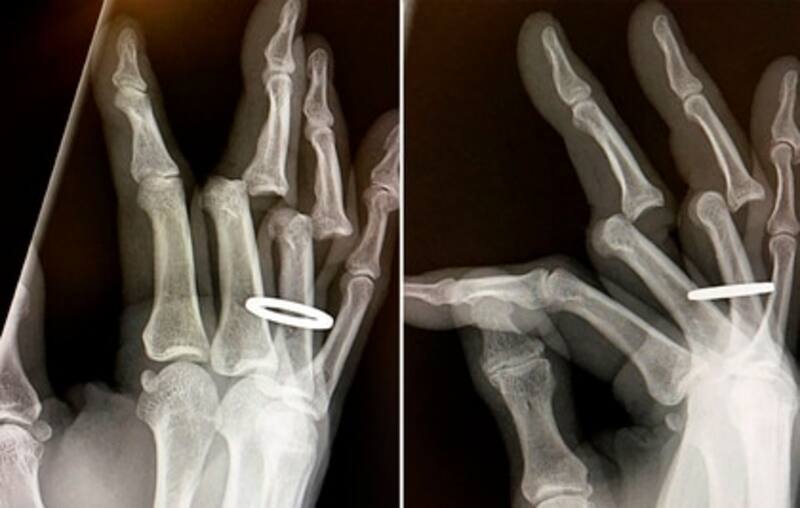

El radiólogo es un médico especialista encargado de elaborar un diagnóstico clínico a través de las distintas modalidades de imagen, que incluyen los rayos X (de donde viene el nombre de la especialidad, a pesar de que actualmente constituye menos del 10% de su actividad), ultrasonido, tomografía computada y resonancia magnética. Estas técnicas de imagen permiten además guiar procedimientos diagnósticos y terapéuticos percutáneos mínimamente invasivos reemplazando técnicas quirúrgicas.

Por su parte, el TAC o tomografía computarizada es un estudio de rayos X que obtiene imágenes del cuerpo utilizando radiación ionizante, mientras que la resonancia utiliza un campo magnético y ondas de radiofrecuencia, que no son nocivas para el paciente, por lo cual se puede utilizar en niños y embarazadas. Son estudios diferentes que no necesariamente compiten entre sí, pues hay diagnósticos en los cuales la tomografía computada es más específica respecto a la resonancia magnética y viceversa.